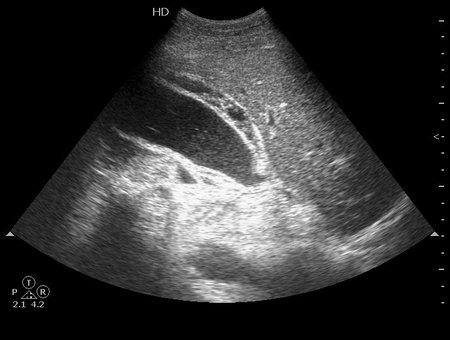

УЗИ желчного пузыря - ферментативный ОХ при ОП

Мужчина средних лет, болен хроническим панкреатитом. Поступил в хирургическое отделение с резкими болями в животе.

гангренозный деструктивный холецистит

Serg писал(а):гангренозный деструктивный холецистит

В принципе все нормально, но нужно добавить еще одно слово.

Это типичная презентация особой формы острого холецистита.

Нет, не это слово, хоть пузырь и перфоративный.Serg писал(а):жидкость по нижнему контуру - перфоративный?

Нет, но могут быть. Это не слово "калькулезный" или "бескаменный".HELEN писал(а):В этом ЖП есть конкременты?

Ишемический холецистит?

Нет.valeriy.andilevko писал(а):Ишемический холецистит?

Эмфизематозный....